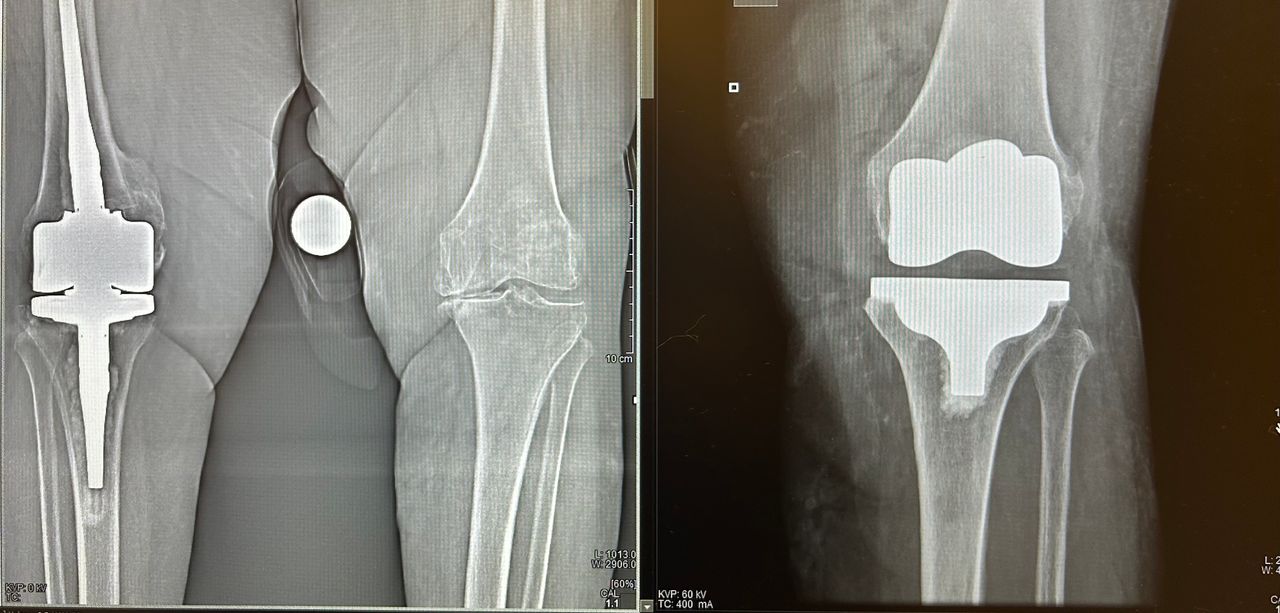

• Chirurgia del ginocchio

Per una maggiore completezza della visita è utile avere a dispozione almeno una Radiografia standard o Risonanza Magnetica recenti.

Il Dottor Luca Luciano si è dimostrato un professionista di grande competenza e umanità. Fin dal primo incontro ha saputo spiegare con chiarezza ogni dettaglio dell’intervento all’anca, rassicurandomi e facendomi sentire sempre seguito.

Nonostante il mio fosse un caso complesso, ha affrontato la situazione con sicurezza e determinazione, proponendo un intervento di protesi d’anca con tecnica mini-invasiva. Il decorso è stato sorprendentemente rapido e il risultato finale eccellente.

Oltre alla bravura chirurgica, ciò che fa davvero la differenza è la sua vicinanza al paziente: sempre disponibile, attento e capace di trasmettere fiducia anche nei momenti più difficili.